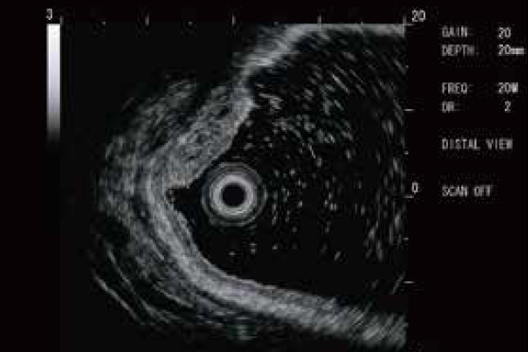

High-resolution ultrasonic images can be obtained through the digital video signal output and digital correction of the imaging artifacts.

20MHz